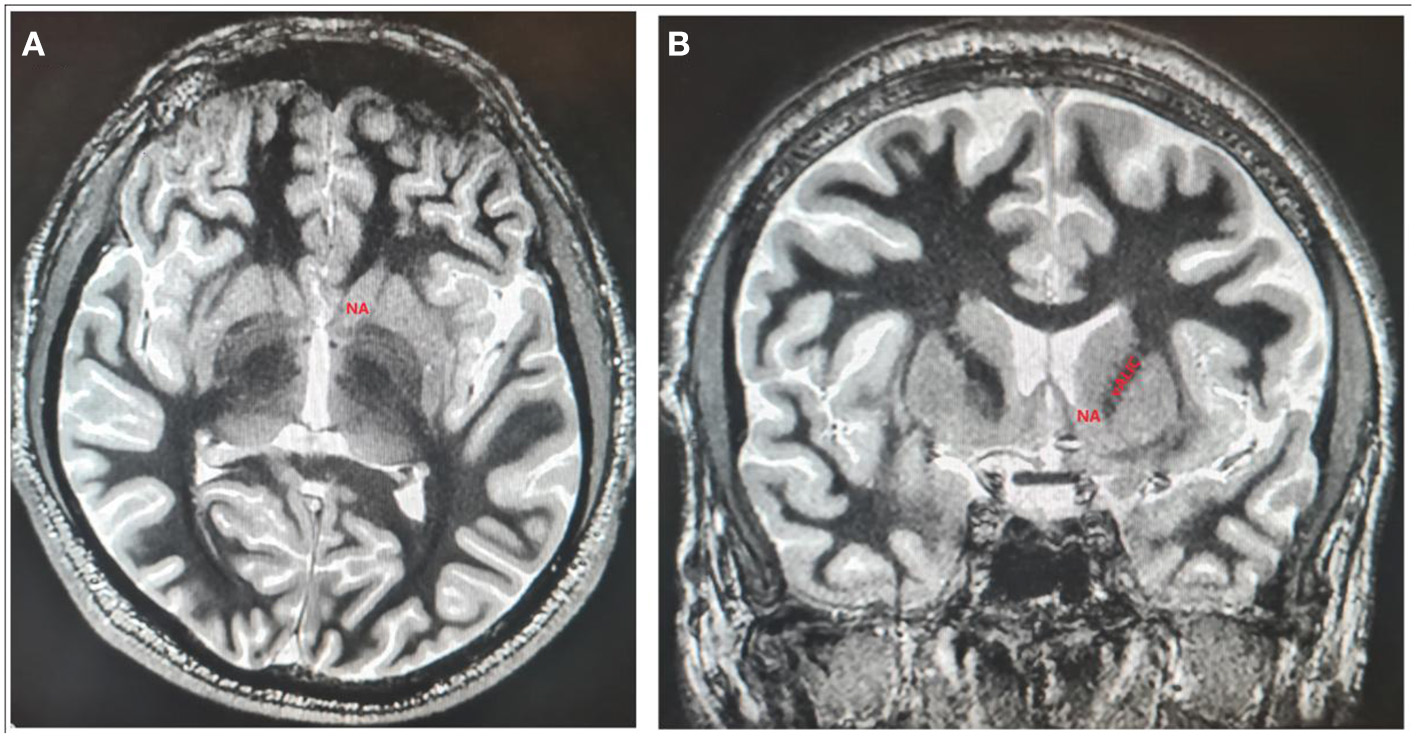

Figure 3

The localization of NAc and vALIC presented on axial (A) and coronal (B) sections of 3D T1-weighted imaging white/matter null sequence.